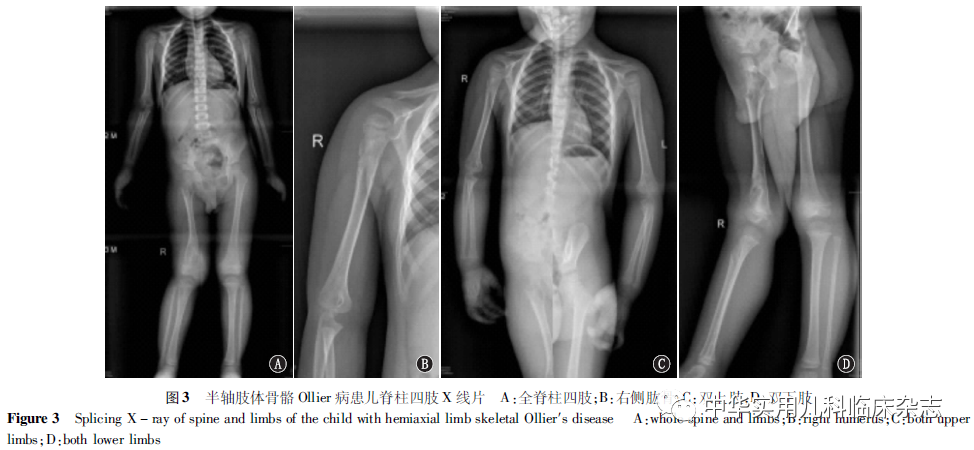

临床资料回顾性分析。患儿,男,3岁,因“发现右下肢跛行2 d”入院。2  d前家属无意间发现患儿行走时右下肢跛行,患儿无明确外伤史及感染史,后未见好转,家属为求进一步诊治来诊。入院查体:神志清楚,生命体征平稳,双下肢不等长,右下肢较对侧短缩约1 cm,双髋关节及膝关节局部无红肿及压痛,右膝关节外翻畸形,双髋关节屈曲、内收、外展及内外旋活动不受限,肢端感觉、血运及足趾活动未见明显异常;辅助检查:骨盆X线片提示右侧骨盆及右股骨近端多发病变,CT提示右侧髂骨、股骨近端、耻骨多发病变,考虑组织细胞增生症(图1)。初步诊断:(1)右侧股骨颈及大转子、右侧骨盆(髂骨及耻骨)多发病变原因:组织细胞增生症?(2)右膝关节外翻畸形。本研究通过遵义医科大学附属医院医学伦理委员会批准(批准文号:KLL-2020-314),患儿监护人知情同意,并签署知情同意书。入院后行骨盆磁共振成像(MRI)提示右侧髂骨、耻骨及右股骨上段多发病变,考虑组织细胞增生症(图2),胸部平片发现右肱骨上段病变,为排除其他部位病变行脊柱四肢X线片检查,结果提示右肱骨上段、右侧髂骨、耻骨、股骨近端、股骨远端、胫腓骨上段、腓骨下段形态不规则,可见多发斑片状、类圆形低密度影,边缘、周围骨质硬化,部分内似有分隔,为多发良性病变,考虑组织细胞增生症可能。余双上肢及双下肢组成骨形态、密度未见异常,各关节对位关系未见异常(图3)。头颅正侧位平片未见异常。结合患儿症状及辅助检查,因患儿右股骨颈、大转子及近端病变范围广,且跛行明显,故行右侧股骨颈及大转子病变刮除、异体骨植骨及石膏外固定术。术中见:右股骨颈及大转子病变处骨膜、关节囊及周围肌肉稍水肿,病变区骨皮质薄、质脆,于病灶处开窗可见病灶近端累及股骨颈骺板,远端累及股骨大转子下缘水平,病变骨组织呈软骨样变;术中处理:彻底刮除病变骨组织,予以浓碘伏、酒精灼烧病变区,9 g/L盐水冲洗,病变区植入同种异体骨12 g,止血,清点器械纱布无误后,逐层缝合,包扎切口,予以右侧半髋石膏固定制动患肢,术中标本送病理检查。术后病理提示:右股骨颈及大转子呈软骨性病变,有分叶状结构,组织破碎,小叶间未见融合,软骨细胞稍丰富,富有黏液样间质,考虑内生性软骨瘤(图4)。出院诊断:(1)右侧肢体肱骨上段、骨盆(髂骨、耻骨)、股骨颈及大转子、股骨下段、胫腓骨上段、腓骨下段多发性内生软骨瘤病;(2)右膝关节外翻畸形。现术后8个月,复查X线片提示植骨处大部分存活,未出现感染、股骨头坏死等并发症(图5),右髋关节功能正常,患儿跛行症状较前好转。

讨论Ollier病为多处骨骼病变,好发于手足等短管状骨,也可见长管状骨及其他骨骼,其本质为内生性软骨瘤同时伴发肢体各种畸形,由于该病发病隐匿,为无痛性骨性病变,常于体检、外伤行X线片检查时意外发现,部分为出现并发症状如跛行、畸形明显时发现。目前文献对该病的报道绝大多数为成年患者,且多为指骨、掌骨等短管状骨病变,儿童病例报道较少,但当病变部位位于干骺端、骨骺甚至骺板时,对儿童骨骼发育影响极大,治疗也相对棘手,易造成残疾。本例患儿即为典型的严重Ollier病,虽家属诉病史仅为2 d,但已出现全身多发骨骼病变,尤其侵犯肱骨上段、髂骨、耻骨、股骨上段(包括大转子、股骨颈及转子间)、股骨下段、胫腓骨上端及胫骨下端,造成右侧下肢过度生长,右膝关节外翻畸形,出现右下肢跛行症状,此外该患儿发病部位仅局限于半轴肢体骨骼,而对侧肢体骨骼发育正常,实属罕见,且易造成误诊,故加强对该病的诊治尤为重要。Ollier病是一种少见的非遗传性良性肿瘤[1],但具有恶变倾向[2],其病因尚不清楚,可能与软骨细胞错构、基因突变[3]等有关。对该病诊断首选影像学检查,典型X线片及CT平扫显示骨干或干骺端膨胀,并可见囊状或柱状骨质缺损或不规则骨质破坏,部分病变区可见数量不等的斑点状、条状及环状钙化[4]。MRI提示大部分患者病变处T1加权像上为低信号,T2加权像上为混合信号[4],增强后显示不均匀强化。但也有少数病例不典型,需与骨囊肿、纤维性骨皮质缺损、代谢性疾病、黏液性纤维瘤、Maffucci综合征[5]、内生性软骨瘤恶变等鉴别。本例患儿MRI提示病灶处以长T1、长T2为主信号影,故考虑组织细胞增生症。对诊断困难者,病理检查仍为金标准,镜下可见分叶状透明软骨,软骨细胞丰富,可富有囊液样间质。针对儿童Ollier病的治疗,作者建议将骨骺病变对骨骼发育的影响降低到最小为原则,积极处理并发症,同时做到长期随访。Ollier病为多发病变,针对肿瘤范围较大、影响骨骺发育、畸形明显部位[6]及引起临床症状的局部病灶需积极手术,主要包括单纯病灶刮除术、病灶刮除+植骨术、病灶扩大刮除+皮质骨重建术等[7],移植骨可根据病灶大小选择,包括自体骨、同种异体骨及磷酸钙骨水泥[8]等。对肢体畸形患儿,可行畸形矫正术,主要包括截骨矫正术(矫正内外翻畸形及其他成角畸形等)、病灶段切除+骨延长术、“8”字钢板暂时性骺阻滞术等。因儿童自我保护意识差,加之好动,故无论采用何种术式,术后均需行石膏或支具固定制动,视病灶处骨骼愈合情况酌情拆除固定,加强患肢功能锻炼。术后并发症主要包括关节僵硬、感染、病理性骨折、畸形复发、延迟愈合、不愈合、神经失用症等,总发生率为27.9%[9]。该病最严重的并发症为内生软骨瘤转化为软骨肉瘤[10],故在长期随访中的疑恶变者,可行病灶活检术,若确诊恶变,应彻底切除或截肢(指/趾),术后辅以相应化疗;其次,该病可侵犯骺板,造成骨骺生长发育紊乱,本例患儿由于股骨颈及大转子病变范围广,已达到股骨头下,易造成股骨头坏死这一灾难后果,故暂行右侧股骨颈、大转子及股骨近端病变刮除、异体骨植骨及石膏外固定术,针对患儿右膝关节外翻畸形,因病变侵犯股骨下段外侧骺板,造成生长发育紊乱,但患儿年龄小,生长发育潜力很大,目前以观察为主,定期随访,必要时可行“8”字钢板暂时性骺阻滞术减缓膝外翻的加剧,右侧下肢的过度生长也需密切观察。综上,Ollier病临床少见,但对于儿童患者,了解其临床表现、病灶分布类型和病理特点,有助于提高诊断水平,并做好长期随访,预防恶性转化和畸形加剧[11]。